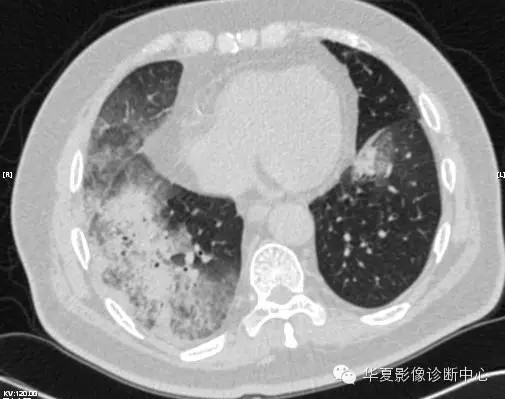

【病例学习】甲型H7N9禽流感一例

男性 63

发热咳嗽5天

2013-4-5拍片示右肺实变,收入院,追问病史,发病期间肌肉酸痛,头痛,无腹痛腹泻,无明显胸闷气急,无意识改变。有高血压病史,无其它病史。

2013-4-7CT进一步检查。

最终诊断:H7N9。